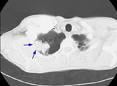

Visceral pleura invasion.

August 21, 2009 - A study published in the August 2009 edition of the Journal of Thoracic Oncology found that non-small cell lung cancer (NSCLC) patients could be more accurately staged at diagnosis by taking into account the level of visceral pleura invasion (VPI). VPI is the extension of a tumor beyond the elastic layer of the visceral pleura.

The status of disease progression is determined through staging by measuring the presence of a localized tumor (T Status), presence of cancerous cells in the lymph nodes (N status) and metastasized tumors (M status). The TNM classification has several subgroups, or stages, that allow physicians to pinpoint the most accurate level of disease progression and develop a treatment plan. Using the International Association for the Study of Lung Cancer’s staging model, Junji Yoshida, MD and his team concluded that a tumor 7cm or less with VPI should be upgraded to the next stage in T status.